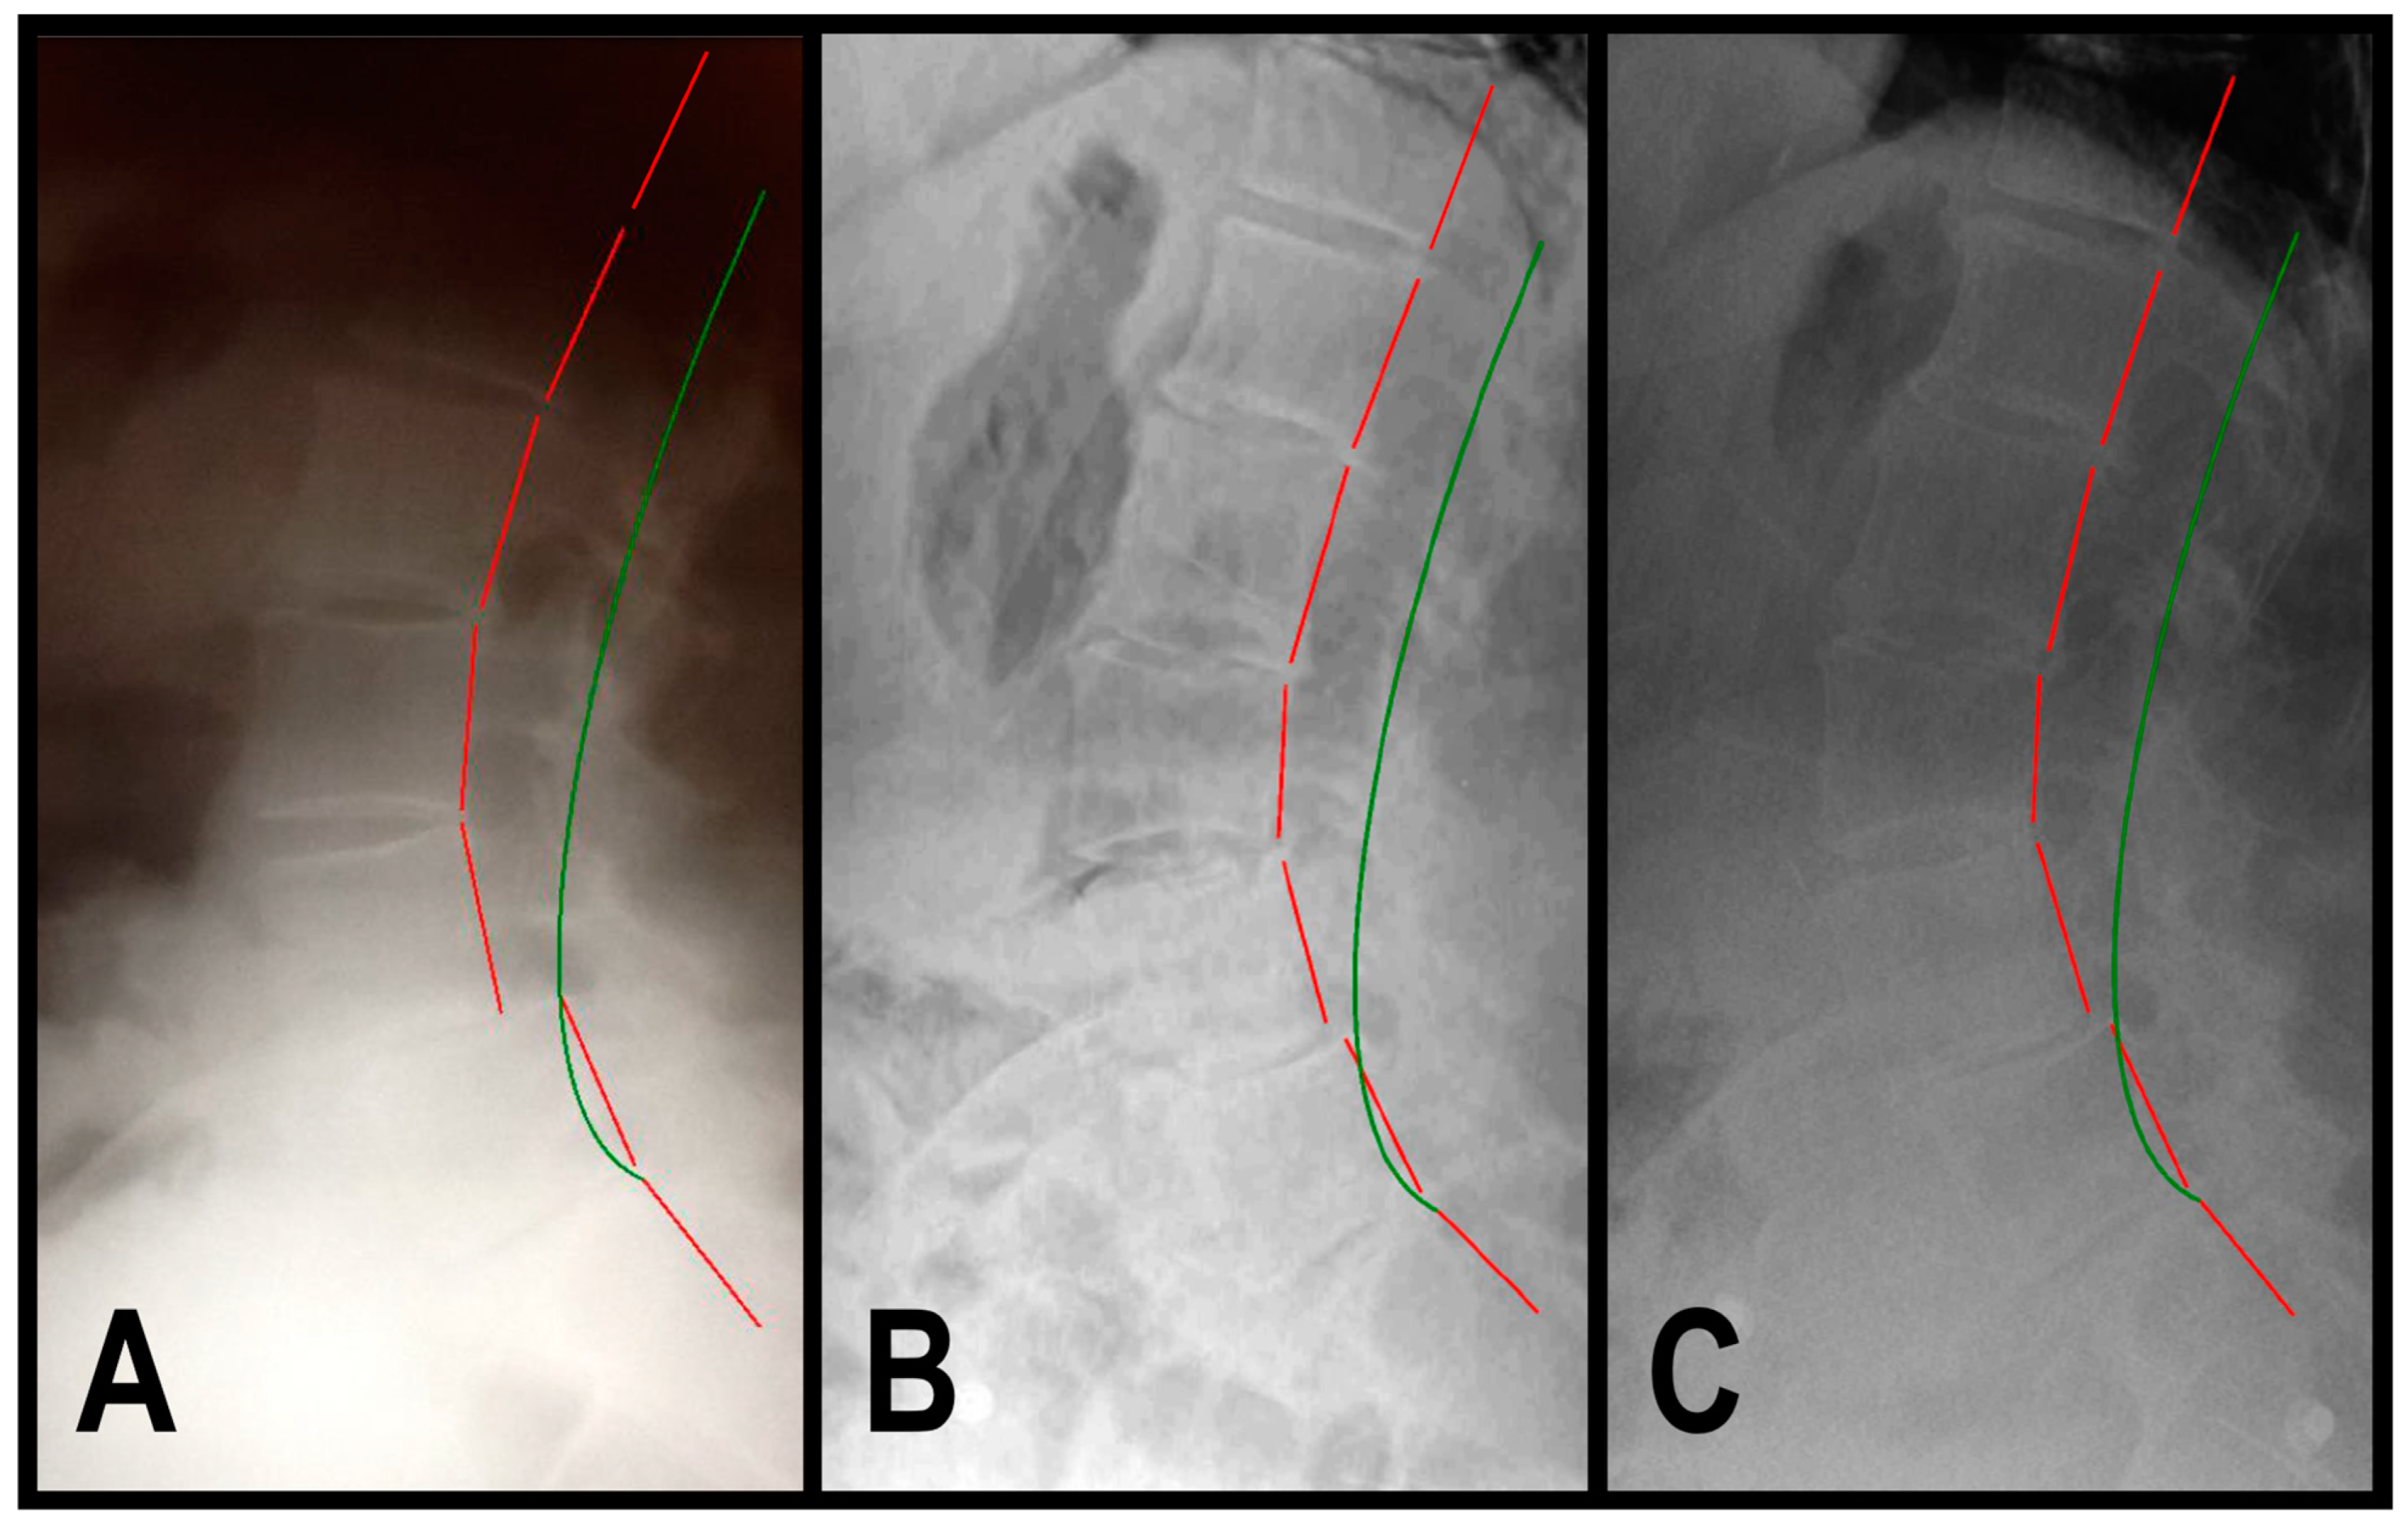

2.3. Radiographic Analysis

3.1.1. Patient 1

3.1.2. Patient 2

3.1.3. Patient 3

| Assessment | Normal Value | Pre-Treatment Exam 3/2015 | Post-Treatment Exam 1/2016 | 3.75-Year Follow-Up Exam 8/2019 | |

|---|---|---|---|---|---|

| Back Pain NRS | 0 | 7 | 1 | 2 | |

| SF-36 HRQOL Scales | PF | 72.0 | 50.0 | 95.0 | 85.0 |

| RP | 81.0 | 25.0 | 80.0 | 75.0 | |

| RE | 81.0 | 66.7 | 90.0 | 100.0 | |

| VT | 61.0 | 40.0 | 70.0 | 70.0 | |

| MH | 81.0 | 52.0 | 76.0 | 72.0 | |

| SF | 83.0 | 60.0 | 100.0 | 87.5 | |

| BP | 75.0 | 50.0 | 90.0 | 87.5 | |

| GH | 72.0 | 50.0 | 85.0 | 80.0 | |

| ΔH | 84.0 | 25.0 | 75.0 | 75.0 | |

| PCS | 46.8 | 35.0 | 54.8 | 51.4 | |

| MCS | 52.8 | 43.5 | 52.7 | 52.8 | |

| ARA L1-L5 (°) | −40 | −51.2 | −45.2 | −45.4 | |

| Tz L5-S1 (mm) | 0 | 13.8 | 4.2 | 4.3 | |

| Urination Frequency (times/24 h) | 0 | 6 | 6 | 6 | |

| Urinary Urgency NRS | 0 | 7 | 2 | 2 | |